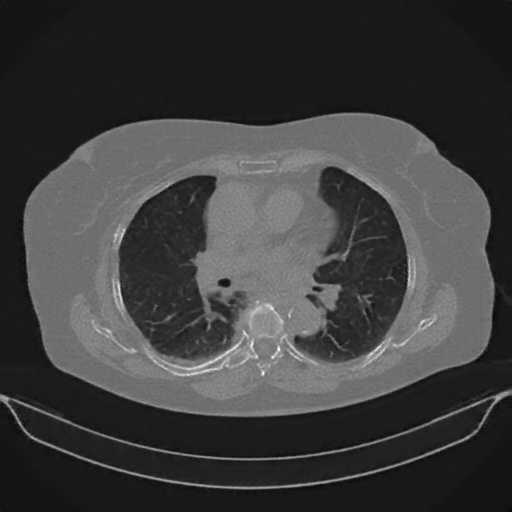

Original NATIVE CT scan (input)

No window - Raw intensity values

Lung window (WL -600, WW 1500 β†’ Low βˆ’1350, High +150)

Mediastinum window (WL 40, WW 400 β†’ Low βˆ’160, High +240)